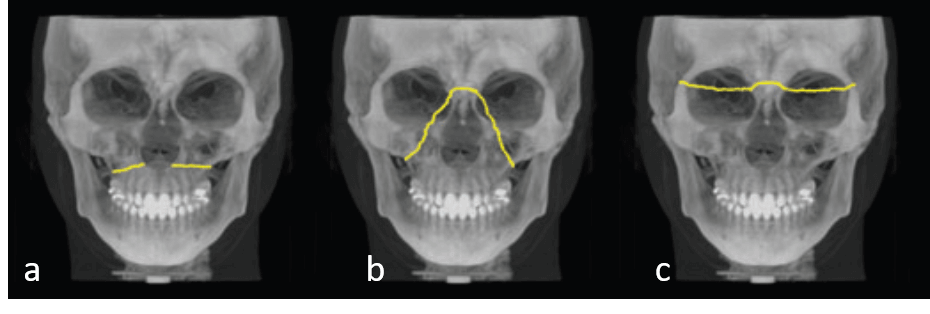

La parte media de la cara comprende los huesos nasal, maxilar y cigomático. Las fracturas en esta región afectan a estructuras que rara vez se fracturan por sí solas, pero que pueden dar lugar, en la mayoría de los casos, a fracturas multifragmentarias o complejas. Estas estructuras son capaces de soportar una fuerza considerable desde abajo, pero son relativamente fáciles de fracturar como resultado de fuerzas normales aplicadas desde otras direcciones. A diferencia de la protección rígida de la mandíbula, las fracturas de la parte media de la cara pueden afectar a varias estructuras importantes, incluida la base del cráneo, que pueden no evaluarse adecuadamente con las imágenes convencionales. La TCCB es capaz de mostrar un mayor número de líneas de fractura y fragmentos en comparación con las imágenes convencionales, representando con precisión la posición y la orientación de los fragmentos desplazados en un intervalo de tiempo razonablemente corto. Clásicamente, los estudios de Rene Le Fort han sido la base para clasificar estos tipos de fracturas ofrecieron una excelente revisión de estas fracturas.

Consideradas comunes en pacientes tras traumatismos faciales contusos, las fracturas del complejo cigomático maxilar son las segundas fracturas faciales más frecuentes después de las fracturas nasales y pueden afectar a las suturas cigomático-frontal, cigomático-temporal y cigomático-maxilar, con fracturas a lo largo de los cigomáticos, el suelo orbitario y el maxilar, lo que da lugar a fracturas trimalar o trípode. Los huesos frontal, etmoidal, palatino, esfenoidal y temporal también pueden verse afectados. En la mayoría de los casos, el seno maxilar se llena de sangre y requiere una intervención en la región periorbital como consecuencia de la fractura de las paredes orbitales. La inflamación de los tejidos blandos asociada al traumatismo puede enmascarar las fracturas cigomáticas, lo que indica la necesidad de realizar imágenes para descartar cualquier afectación de estas estructuras. La TCCB está especialmente indicada porque es capaz de proporcionar excelentes imágenes de las estructuras óseas afectadas y es eficaz para detectar fracturas ocultas o sospechosas antes de la reducción y fijación quirúrgicas.